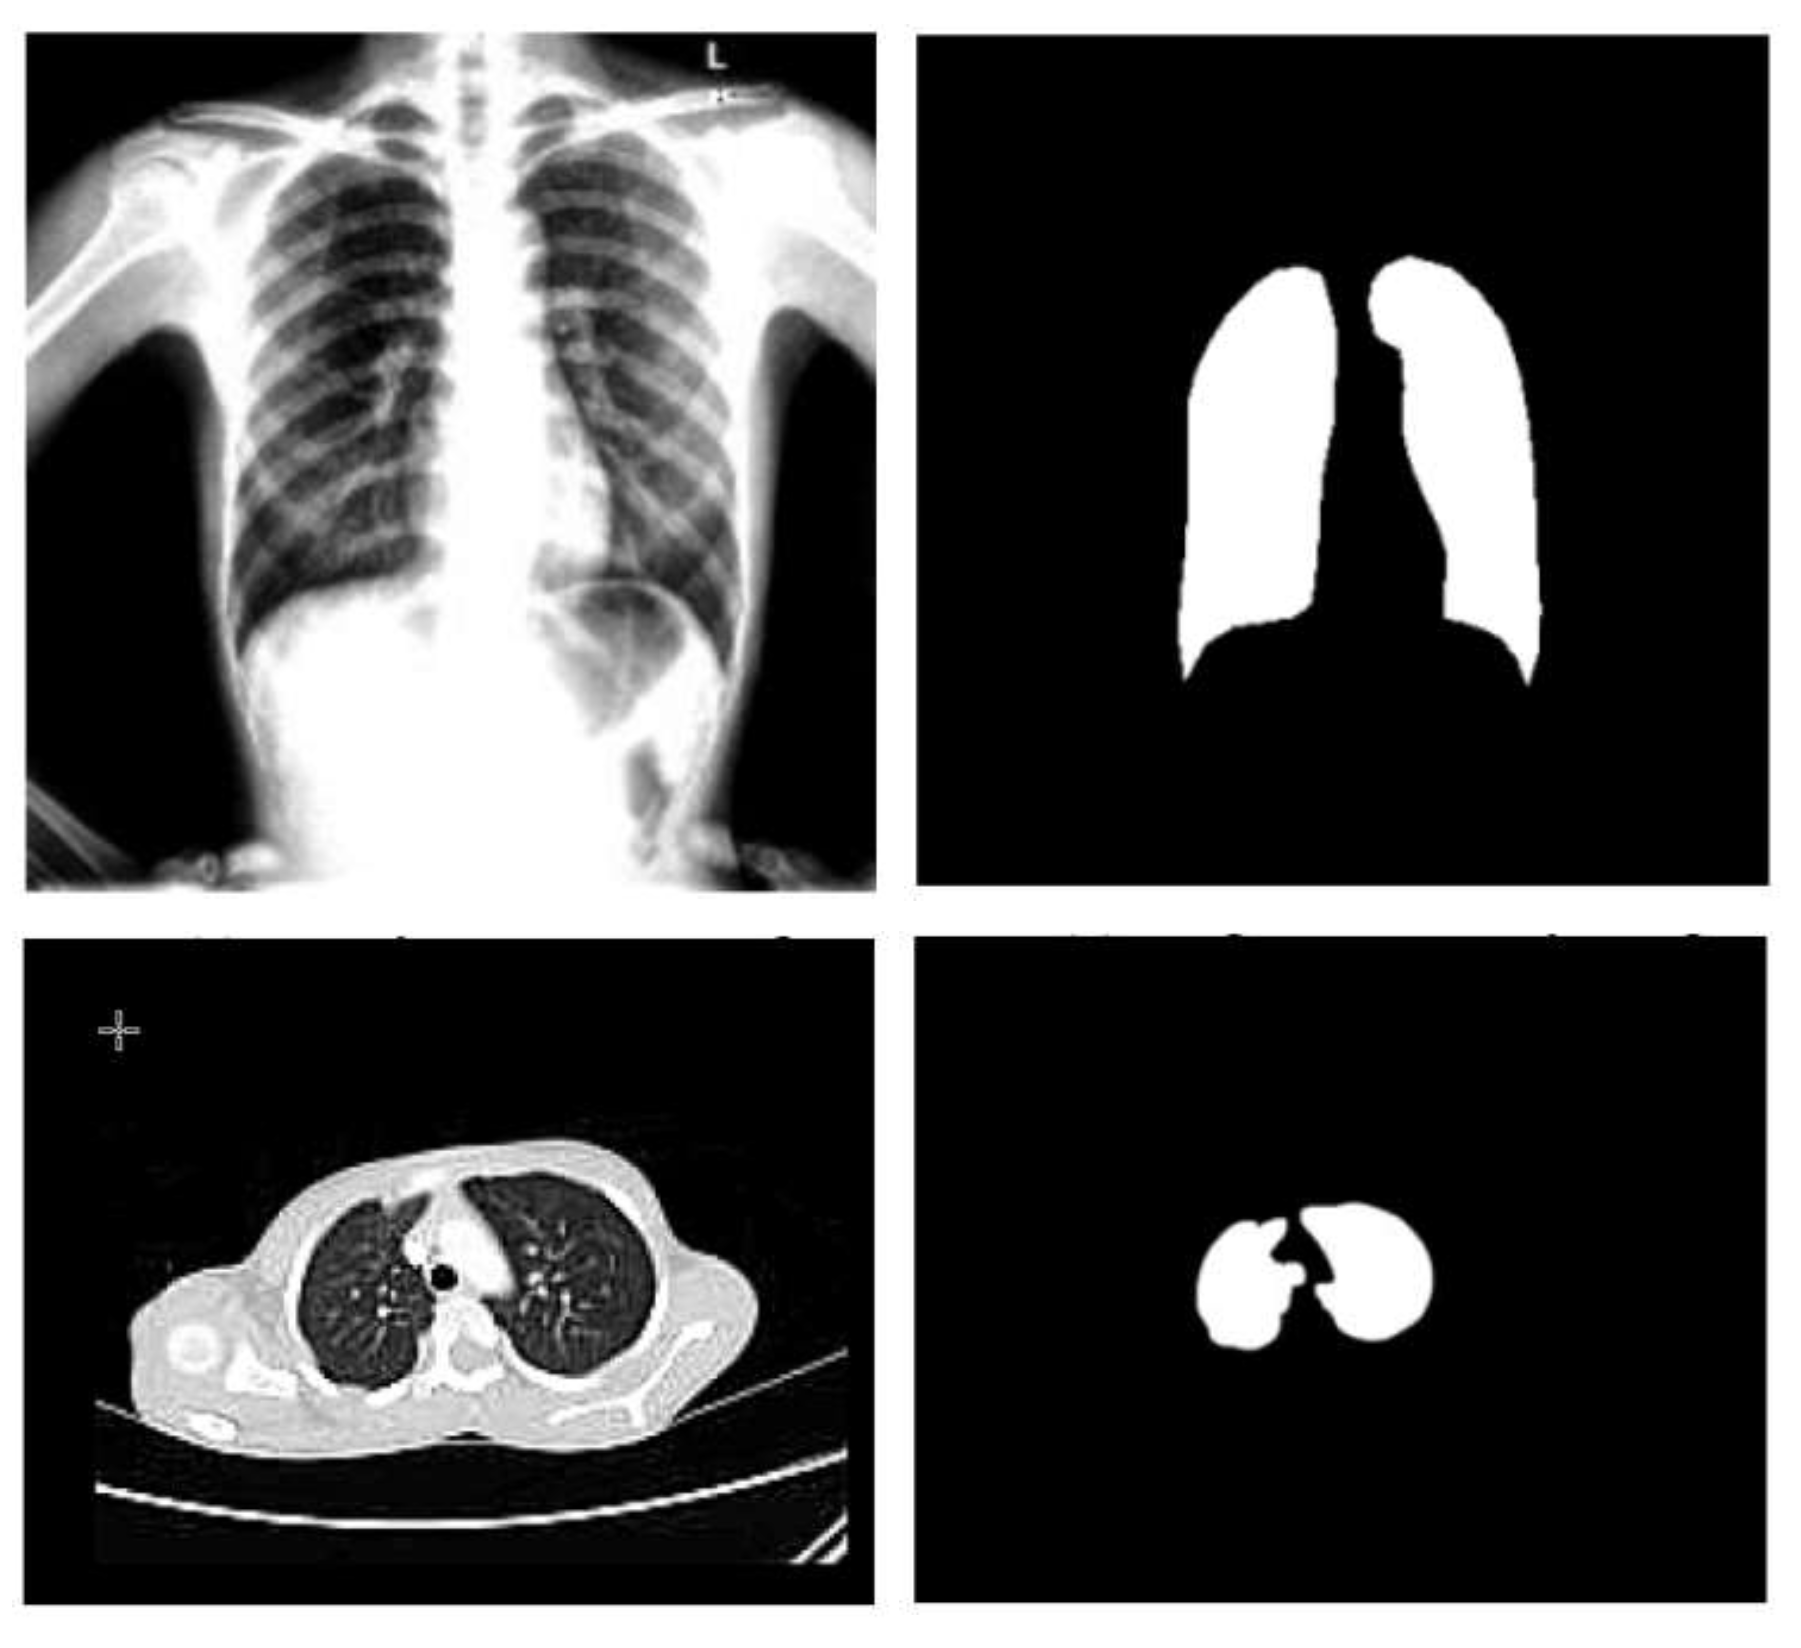

- Normalization: To improve the convergence of the training phase, input pixels to any AI system must have a normalized data distribution. To normalize an image, the distribution’s mean value is first subtracted from each pixel, then divided by the result by the standard deviation. Sample X-ray and CT images are shown in Figure 2 before (on the left) and after (on the right) the preprocessing steps.

3.1.3. Segmentation